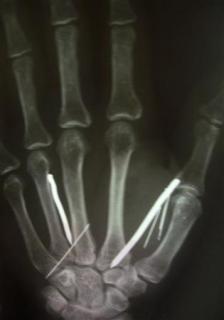

(Reuters) - A Saudi couple tortured their Sri Lankan maid after she complained of a too heavy workload by hammering 24 nails into her hands, legs and forehead, officials said on Thursday.